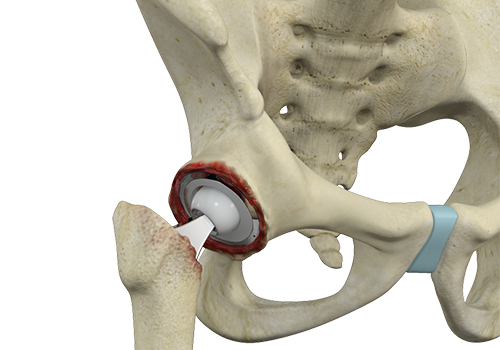

Total hip replacement is a surgical procedure in which the damaged cartilage and bone are removed from the hip joint and replaced with artificial components. The main indication for total hip replacement is arthritis.

Hip replacement surgery is one of the most common orthopedic surgeries performed. It involves the replacement of the damaged hip bone (ball shaped upper end of the femur) with a ceramic ball attached to a metal stem that is fixed into the femur and placing a new cup with a special liner in the pelvis.